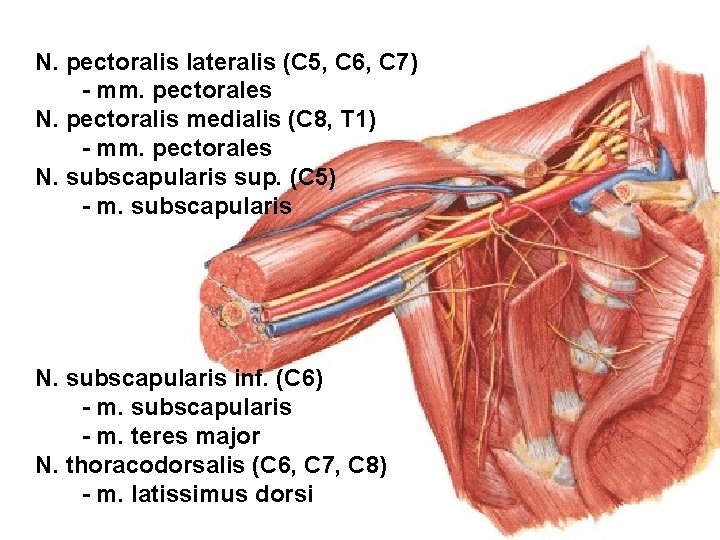

N. pectoralis lateralis (C 5, C 6, C 7) - mm. pectorales N. pectoralis medialis (C 8, T 1) - mm. pectorales N. subscapularis sup. (C 5) - m. subscapularis N. subscapularis inf. (C 6) - m. subscapularis - m. teres major N. thoracodorsalis (C 6, C 7, C 8) - m. latissimus dorsi